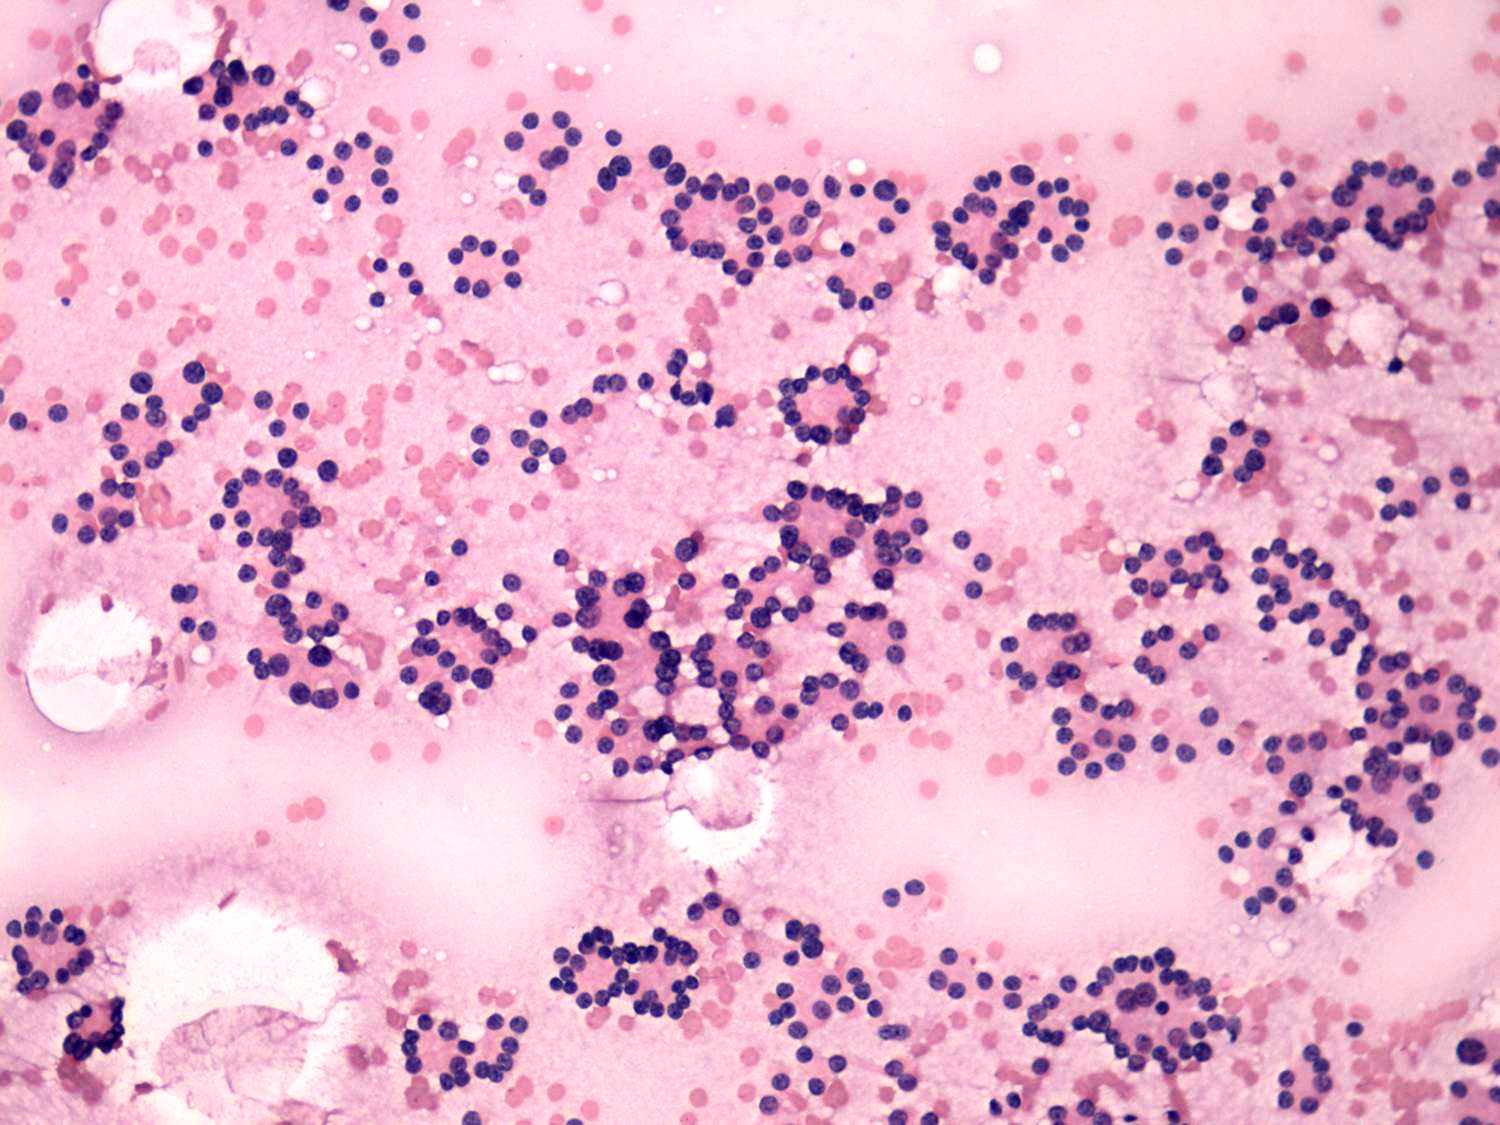

Benign hyperplastic nodule - case 44

Both cases present a microfollicular proliferation. There were several atypical cells in the right case which increased the likelihood of malignant variant of follicular carcinoma.

The right case is even more edifying. Such pattern, i.e. no. colloid in the background, the arrangement of cells almost exclusively in micro- and normofollicles, the monomorphous pattern, the presence of prominent nucleoli, had to be a follicular tumor. However, the nodule proved to be not a follicular tumor but a hyperplastic nodule. This happens in around 10 to 15% of such patterns. If we take the ultrasound presentation into account around half of patients with such cytological presentation can be avoid unnecessary surgery.